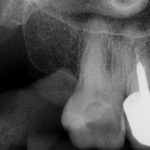

- Paciente do sexo feminino, com 70 anos de idade, nos procurou com queixa de dor no dente 17 (Figura 2).

- Em seguida, relatou ter passado por um profissional que solicitou a ajuda de microscópio por não conseguir descer nos canais. Então, fizemos uma radiografia periapical onde constatou-se atresia em raiz distal, e atresia e curvatura em raiz mesial (Figura 3).

Figura 2 Figura 3 Figura 4 Figura 5 Figura 6 Figura 7